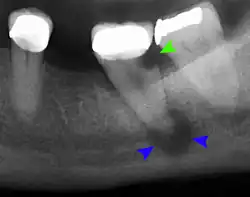

Clinical & xray correlation of pericoronitis

clinical shot of pericoronitis

An operculum (green arrow) over a partially erupted lower left third molar tooth. There is minimal inflammation and recurrent swelling.

xray of pericoronitis

A radiograph of the above tooth showing chronic pericoronitis, operculum (blue arrow) and bone destruction (red arrow) from chronic inflammation. Tooth is slightly disto-angular.

Pericoronitis is inflammation of the soft tissues surrounding the crown of a partially erupted tooth.[25] The lower wisdom tooth is the last tooth to erupt into the mouth, and is, therefore, more frequently impacted, or stuck, against the other teeth. This leaves the tooth partially erupted into the mouth, and there frequently is a flap of gum (an operculum), overlying the tooth. Bacteria and food debris accumulate beneath the operculum, which is an area that is difficult to keep clean because it is hidden and far back in the mouth. The opposing upper wisdom tooth also tends to have sharp cusps and over-erupt because it has no opposing tooth to bite into, and instead traumatizes the operculum further. Periodontitis and dental caries may develop on either the third or second molars, and chronic inflammation develops in the soft tissues. Chronic pericoronitis may not cause any pain, but an acute pericoronitis episode is often associated with pericoronal abscess formation. Typical signs and symptoms of a pericoronal abscess include severe, throbbing pain, which may radiate to adjacent areas in the head and neck,[21][26]: 122  redness, swelling and tenderness of the gum over the tooth.[27]: 220–222  There may be trismus (difficulty opening the mouth),[27]: 220–222  facial swelling, and rubor (flushing) of the cheek that overlies the angle of the jaw.[21][26]: 122  Persons typically develop pericoronitis in their late teens and early 20s,[28]: 6  as this is the age that the wisdom teeth are erupting. Treatment for acute conditions includes cleaning the area under the operculum with an antiseptic solution, painkillers, and antibiotics if indicated. After the acute episode has been controlled, the definitive treatment is usually by tooth extraction or, less commonly, the soft tissue is removed (operculectomy). If the tooth is kept, good oral hygiene is required to keep the area free of debris to prevent recurrence of the infection.[21]: 440–441